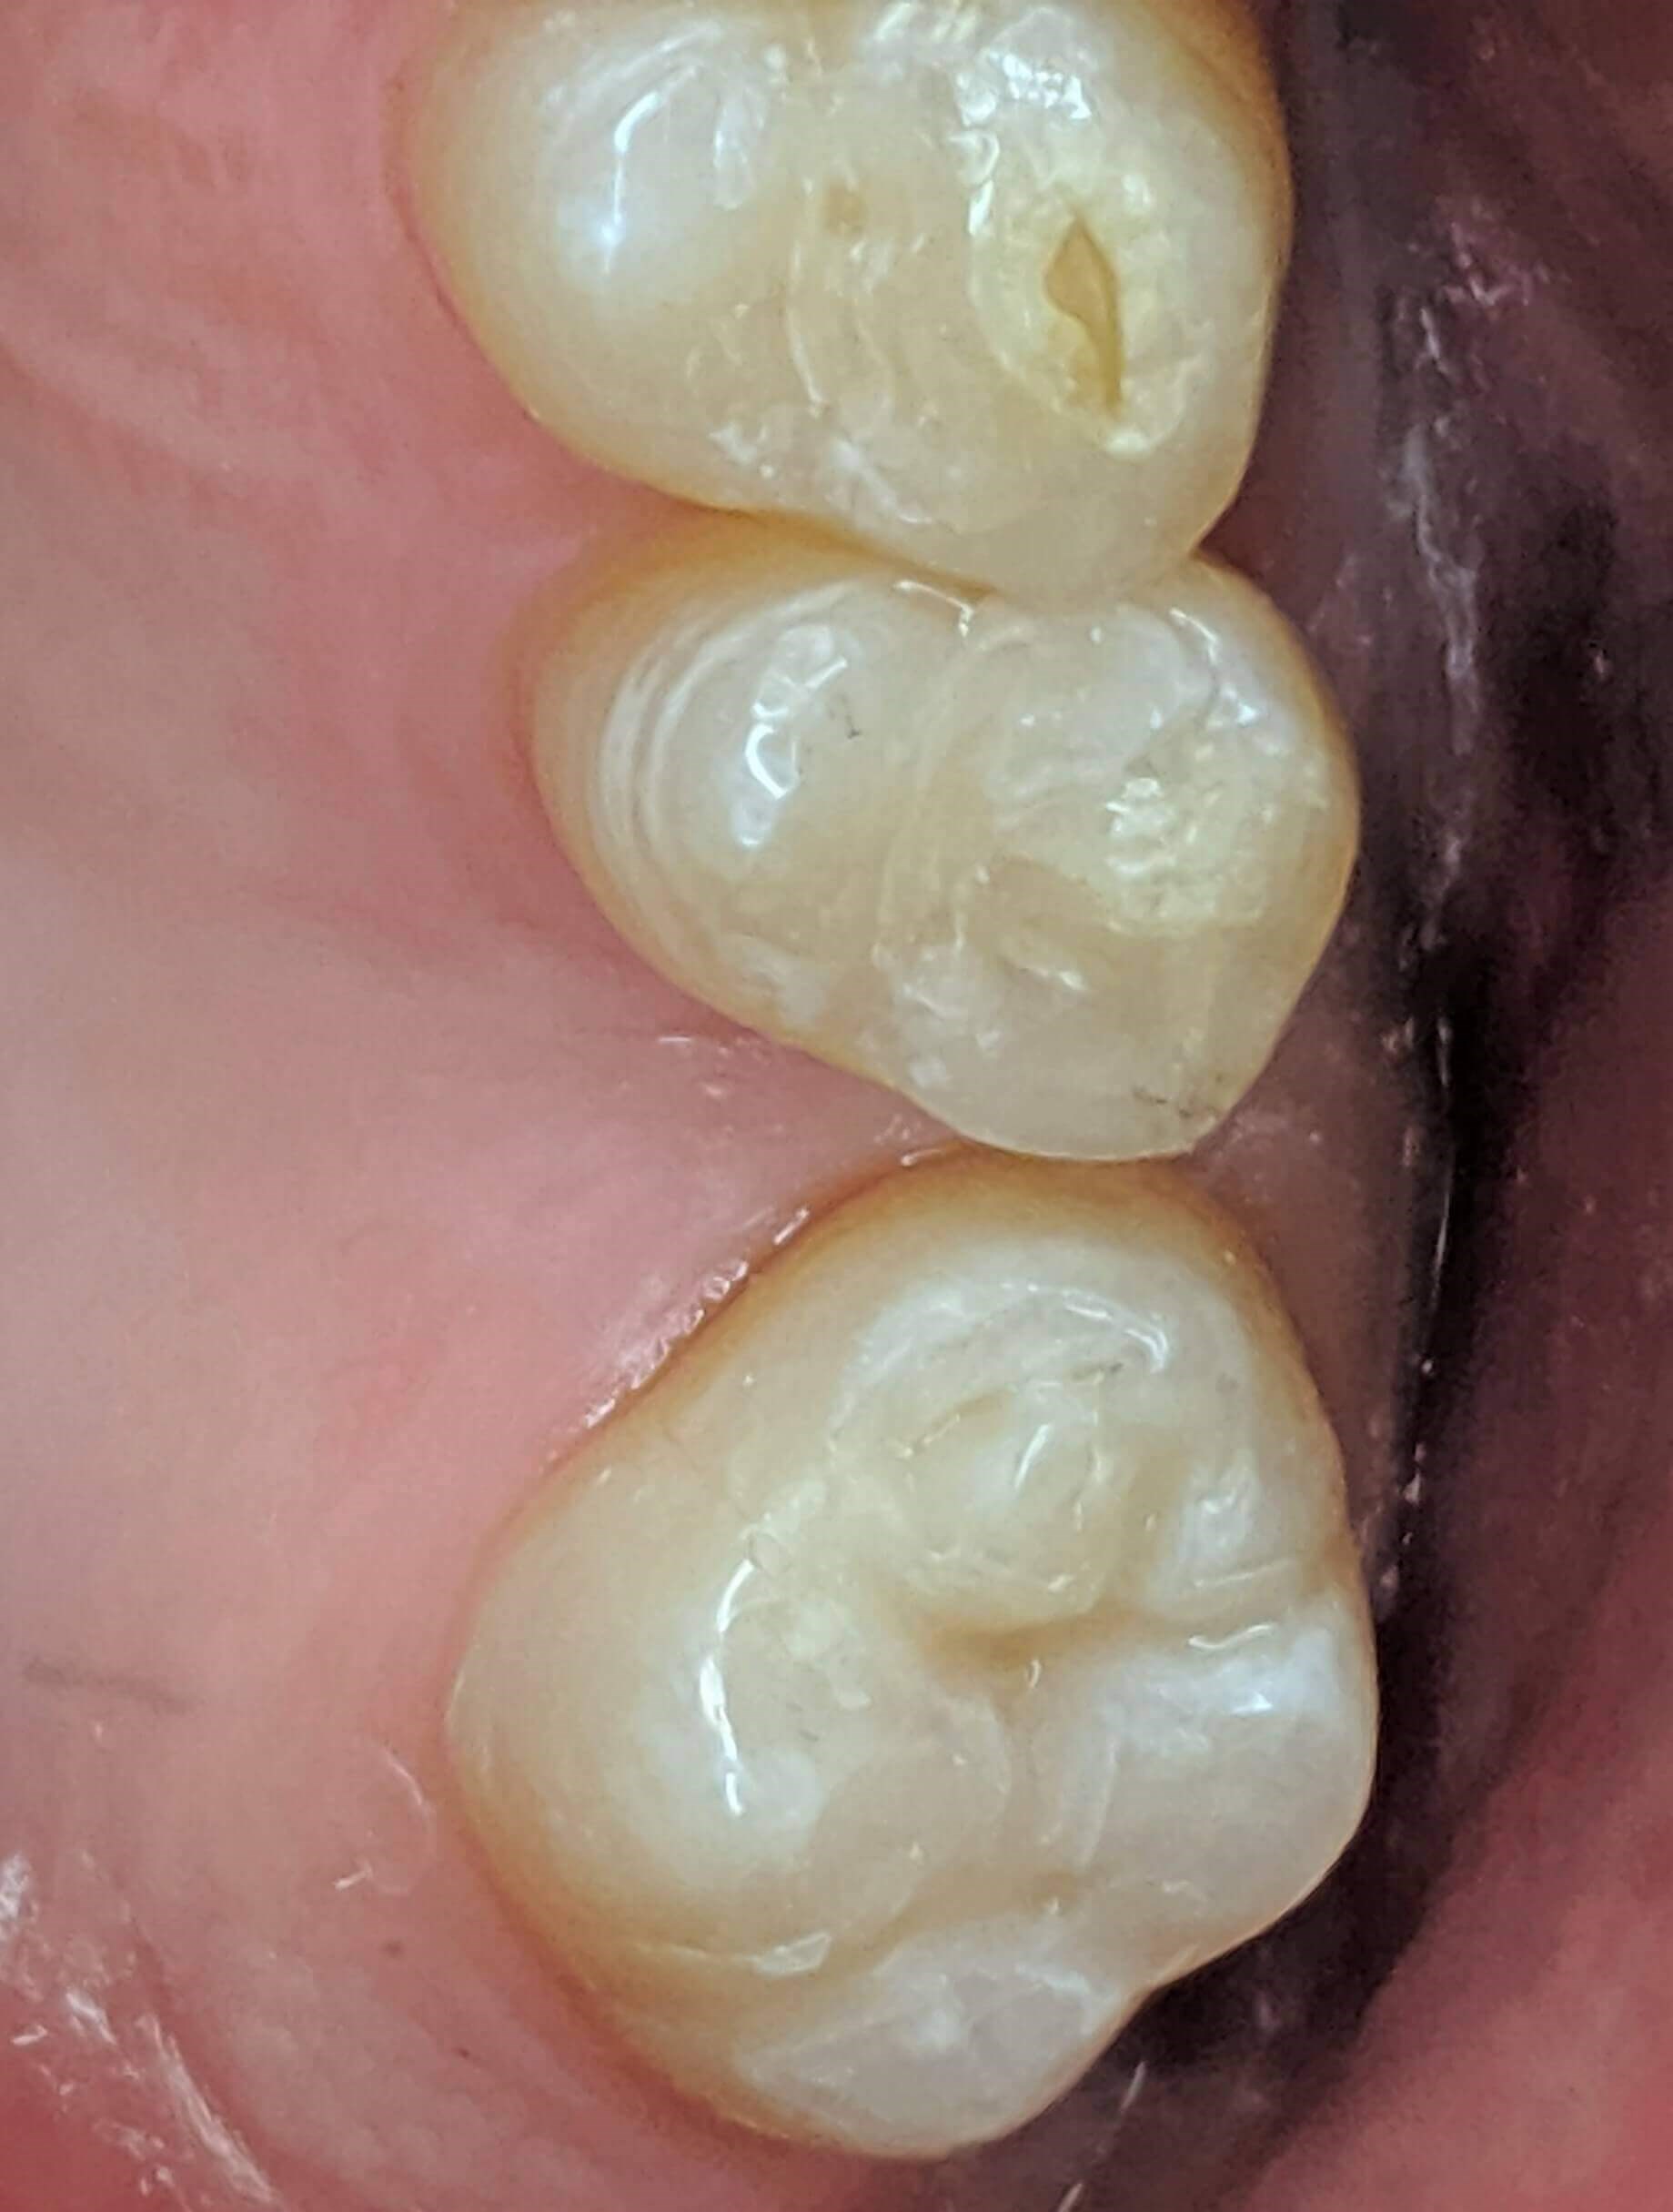

Tooth-colored fillings often fill in the decay in the enamel after it has been cleaned. Composite resin is a versatile material that can be used to treat other problems with your teeth, including cracks or enamel that has been worn down by teeth grinding (bruxism). Since the composite resin is colored to match your natural teeth, tooth-colored fillings can be used on both the front and back teeth for a seamless appearance. If you have metal fillings, talk to Dr. Kim or Dr. Chang about having them removed and replaced with tooth-colored fillings.

Getting a filling at Luminous Dental Studio is typically an easy process. The area surrounding the cavity will be numbed with a local anesthetic to minimize your discomfort. Other forms of sedation can be discussed if you have any fears or dental anxieties to help keep you at ease during the procedure. Once you are prepared, the decayed enamel is removed with a unique dental drill that Dr. Kim or Dr. Chang will select based on where the cavity is located in the tooth and the level of decay. After the enamel is removed and the tooth is cleaned, the cavity will be filled with the composite material and set with a special light. Dr. Kim or Dr. Chang will polish the filling so it feels comfortable and matches your natural teeth.

Yes, they do. The main benefit of tooth-colored fillings is the fact that they don't change the natural color of your tooth — so no one but you will know you have a filling.